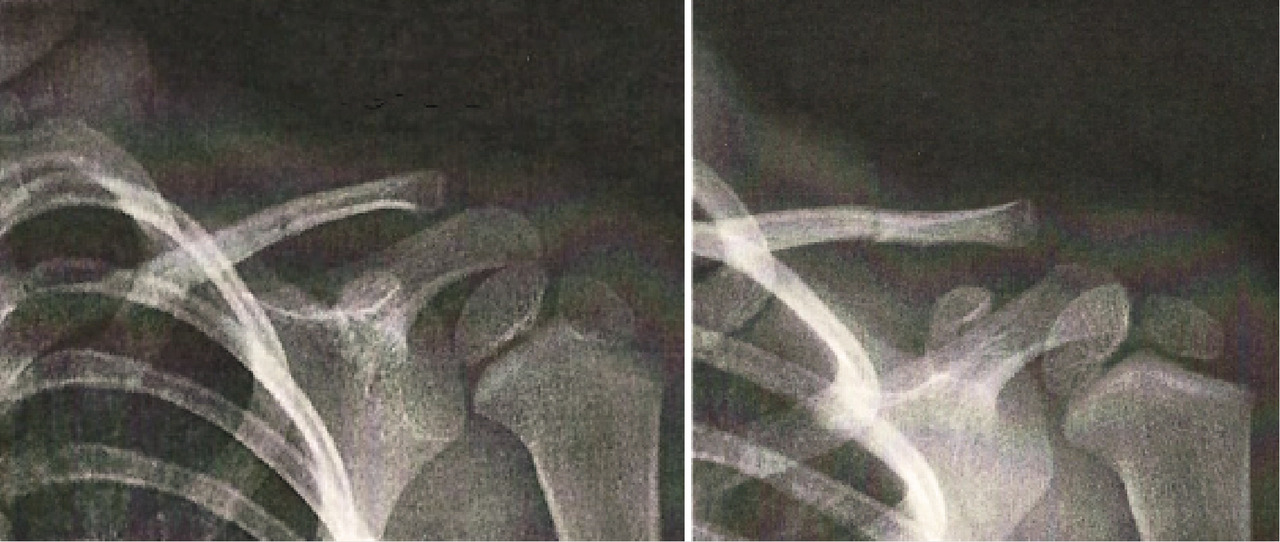

Le jeune Théo, 4 ans, consulte avec sa mère pour un défaut de mobilité du membre supérieur gauche apparu depuis quarante-huit heures. Lors de l’examen clinique, il lui est impossible de mobiliser le bras gauche en antépulsion ou en rétropulsion. Aucune douleur n’est par ailleurs relevée. Devant cette situation, une radiographie est réalisée (figure).

Le tiers moyen est le plus souvent touché (entre 70 et 80 % des cas) ; le tiers interne ou externe, plus rarement.

Le diagnostic est souvent porté tardivement car les parents ne prêtent pas nécessairement attention à un déficit léger, de surcroît non forcément exprimé par l’enfant. Il repose sur la réalisation d’une radiographie de l’épaule de face et d’un profil de Lamy, visualisant parfaitement la scapula.